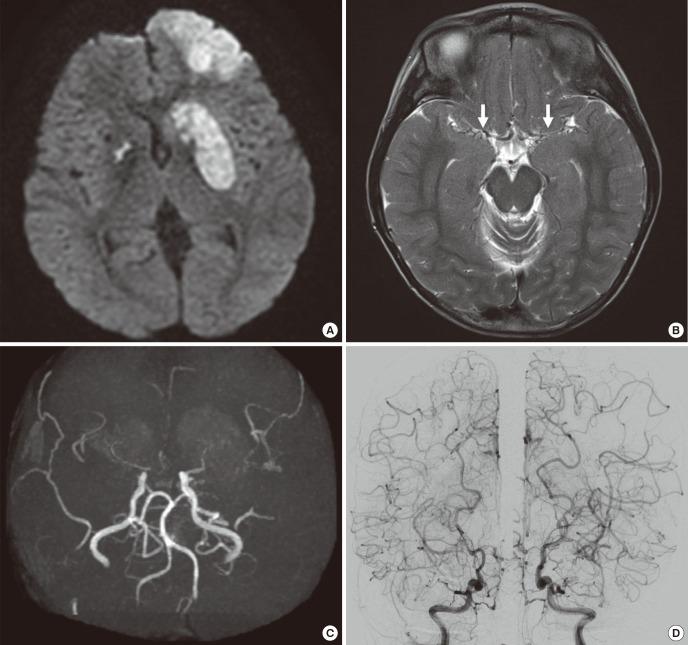

Radiotherapy is one of the standard treatments for medulloblastoma. However, therapeutic central nervous system irradiation in children may carry delayed side effects, such as radiation-induced tumor and vasculopathy. Here, we report the first case of coexisting meningioma and moyamoya syndrome, presenting 10 years after radiotherapy for medulloblastoma. A 13-year-old boy presented with an enhancing mass at the cerebral falx on magnetic resonance imaging (MRI) after surgery, radiotherapy (30.6 Gy craniospinal axis, 19.8 Gy posterior fossa) and chemotherapy against medulloblastoma 10 years ago, previously. The second tumor was meningioma. On postoperative day 5, he complained of right-sided motor weakness, motor dysphasia, dysarthria, and dysphagia. MRI revealed acute cerebral infarction in the left frontal lobe and both basal ganglia. MR and cerebral angiography confirmed underlying moyamoya syndrome. Four months after the meningioma surgery, the patient presented with headaches, dysarthria, and dizziness. Indirect bypass surgery was performed. He has been free from headaches since one month after the surgery. For patients who received radiotherapy for medulloblastoma at a young age, clinicians should consider the possibility of the coexistence of several complications. Careful follow up for development of secondary tumor and delayed vasculopathy is required.

放射治疗是髓母细胞瘤的标准治疗方法之一。然而,儿童中枢神经系统放射治疗可能会带来延迟性副作用,如放射性肿瘤和血管病变。在此,我们报告首例在髓母细胞瘤放疗10年后同时出现脑膜瘤和烟雾病综合征的病例。一名13岁男孩10年前曾接受髓母细胞瘤手术、放疗(全脑全脊髓轴30.6 Gy,后颅窝19.8 Gy)及化疗,此次磁共振成像(MRI)检查发现大脑镰处有一强化肿块。第二个肿瘤为脑膜瘤。术后第5天,他出现右侧肢体运动无力、运动性失语、构音障碍和吞咽困难。MRI显示左侧额叶及双侧基底节区急性脑梗死。磁共振血管造影和脑血管造影证实存在潜在的烟雾病综合征。脑膜瘤手术后4个月,患者出现头痛、构音障碍和头晕。遂进行了间接搭桥手术。术后1个月起患者头痛症状消失。对于幼年接受髓母细胞瘤放疗的患者,临床医生应考虑多种并发症并存的可能性。需要对继发性肿瘤和延迟性血管病变的发生进行密切随访。